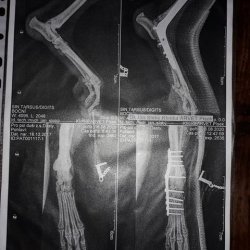

Dasty na operaci s nohou

Dastíka už všichni znáte. Je to svěřenec neziskové organizace Pro psí duši, z.s., kterému jsme přispívali na amputaci ocásku v květnu tohoto roku. Již v květnu RTG u Dastíka odhalil, že měl zlomenou páteř a jeho zadní nožky, pravděpodobně právě po zranění páteře, zůstaly ochromené. Tím došlo k atrofii svalstva, uvolnění šlach u úponů k prstíkům na zadních nožkách. Dasty se nemohl na nožičky normálně postavit a chodil po patách. Nyní je Dasty po operaci první nožičky. Operace byla velikým a nákladným zákrokem. Dasty je ovšem obrovský bojovník s pravým psím srdíčkem. Na listopad je naplánovaná operace druhé nožičky.